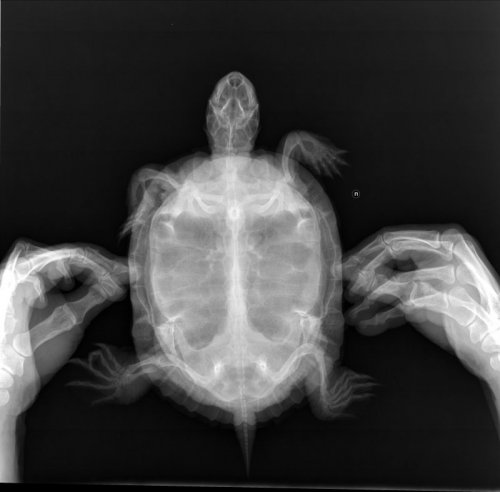

Консультанты moth Ваше имя: Мария Локация: Москва Опубликовано: 7 апреля 2021 Консультанты Опубликовано: 7 апреля 2021 @Galina_tag Константин обещал ответить сегодня, но не знаю ответит или нет. Сделайте в трёх, если финансы позволяют дорсовентральной, правой латеральной и кранио-каудальной. 1

Galina_tag Ваше имя: Галина Локация: Россия, Таганрог Опубликовано: 8 апреля 2021 Автор Опубликовано: 8 апреля 2021 (изменено) @moth Здравствуйте! Сделали рентген. Изменено 8 апреля 2021 пользователем Galina_tag

Galina_tag Ваше имя: Галина Локация: Россия, Таганрог Опубликовано: 8 апреля 2021 Автор Опубликовано: 8 апреля 2021 (изменено) @moth А Вы можете рентген прокомментировать? Пневмонии нет, насколько я понимаю? Может, нам кальций уколоть? Изменено 8 апреля 2021 пользователем Galina_tag

Консультанты moth Ваше имя: Мария Локация: Москва Опубликовано: 8 апреля 2021 Консультанты Опубликовано: 8 апреля 2021 @Galina_tag я всё-таки надеюсь Константин ответит сегодня, я ему днём снимки все скинула. Я плохо умею читать снимки, но я бы сказала, что у неё легкие сдавлены либо желудком либо фолликулами. Тут да, скорее всего нужен будет кальций.

Galina_tag Ваше имя: Галина Локация: Россия, Таганрог Опубликовано: 10 апреля 2021 Автор Опубликовано: 10 апреля 2021 10 часов назад, moth сказал: @Galina_tag Но если Вам вдруг ответят в инсте - попробуйте договориться там с врачом, я думаю сейчас так будет быстрее. Буду с Вами честной и объективной. Я не знаю на сколько тут затянется переписка, а время терять не хочется. Один из врачей ответил, что с легкими и кишечником все нормально. Самое вероятное - витологенез (овуляция). Кальций можно не колоть или немного - 2-3 раза. До месяца могут не есть - это норма. Второй отозвался, но пока ничего не написал.

Консультанты moth Ваше имя: Мария Локация: Москва Опубликовано: 10 апреля 2021 Консультанты Опубликовано: 10 апреля 2021 @Galina_tag Константин ответил, что по рентгену скорее опять проблемы с жкт, т.к. хек это не еда для красноухой и при таком рационе Вы её каждый год лечить будете. Я сама пропустила этот момент в анкете. Она же опять ничего толком не получает из морской рыбы. Он порекомендовал кальций через день курс 5 инъекций, вибротерапию раз в день и уколы Серении. Поищите, сможете ли в ветклинике купить Серению. Она очень дорогая чтобы флакон покупать. 1